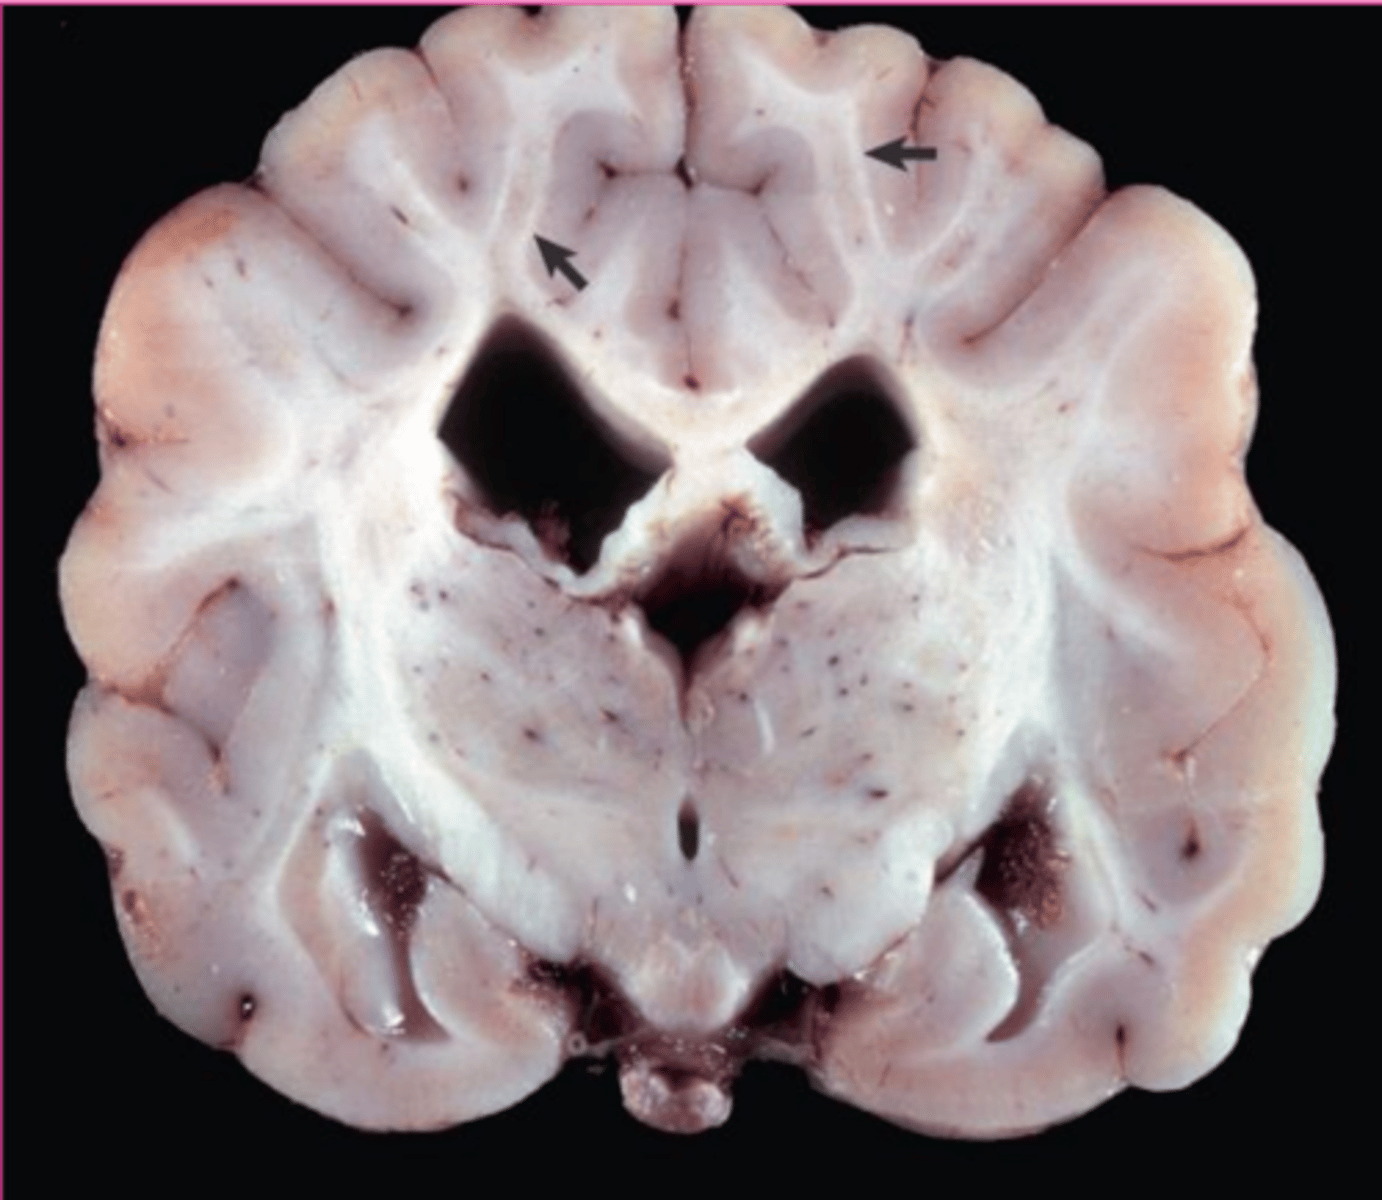

globoid cell leukodystrophy

What?